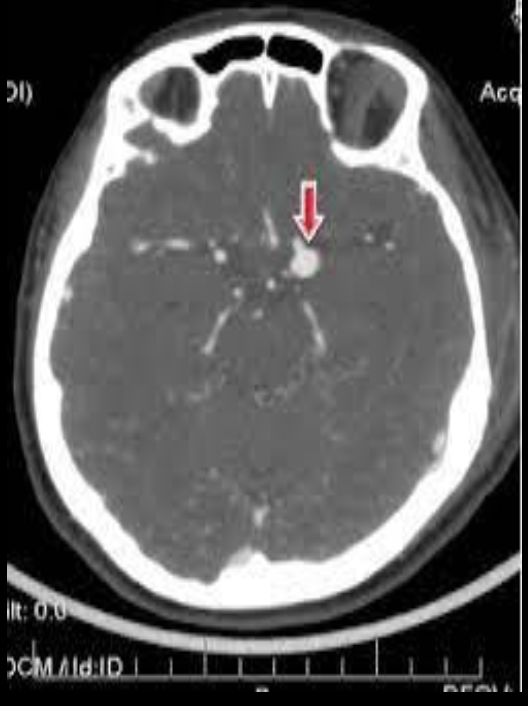

A

EVC hemorragico

AngioTC